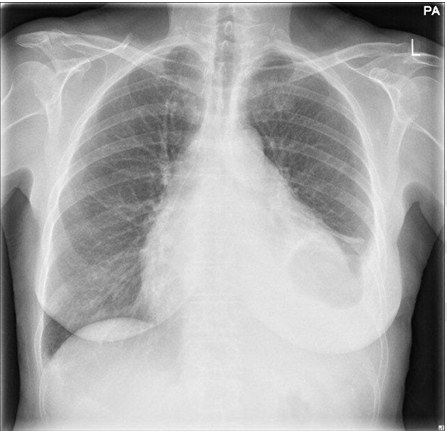

The patient was adequately resuscitated with oxygen therapy and intravenous fluids, and analgesia was escalated to intravenous morphine, but with no success, as pain relief was not achieved. Routine investigations were sent. Thyroid function tests, immunoglobulin levels, complement levels, and creatine kinase were all normal. All electrolytes were within normal limits. Autoantibody screen, including ANCA, ANA and ENA, was negative. Hematinics, including vitamin B12 were normal. Liver and renal function were normal, as were clotting times. The only abnormal results from the bloods tested were her full blood count, her CRP and her serum IgE levels. The patient was anemic with hemoglobin of 10.8 g/dl (normocytic, normochromic), and her white cell count was raised to 25.2x109/L, with marked eosinophilia of 17.6 (x109/L). Her platelets were raised at 507x109/L. Her CRP was 120 (mg/L) (normal range 0-4 mg/L) and her IgE levels were 148 (U/L) (normal range <75U/L). Arterial blood gas was obtained, which revealed mild hypoxia. Chest X-ray revealed a small left sided pleural effusion (Figure 1).

Cursor on image to zoom/Click text to open image

Figure 1: Chest X-ray on admission showing unilateral pleural effusion.